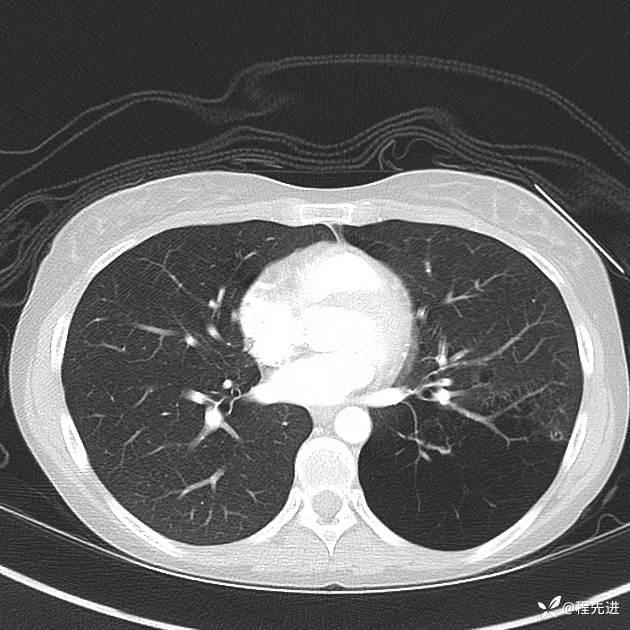

患者性别:女

患者年龄:25岁

简要病史:下胸部疼痛3天

CT增强:

img